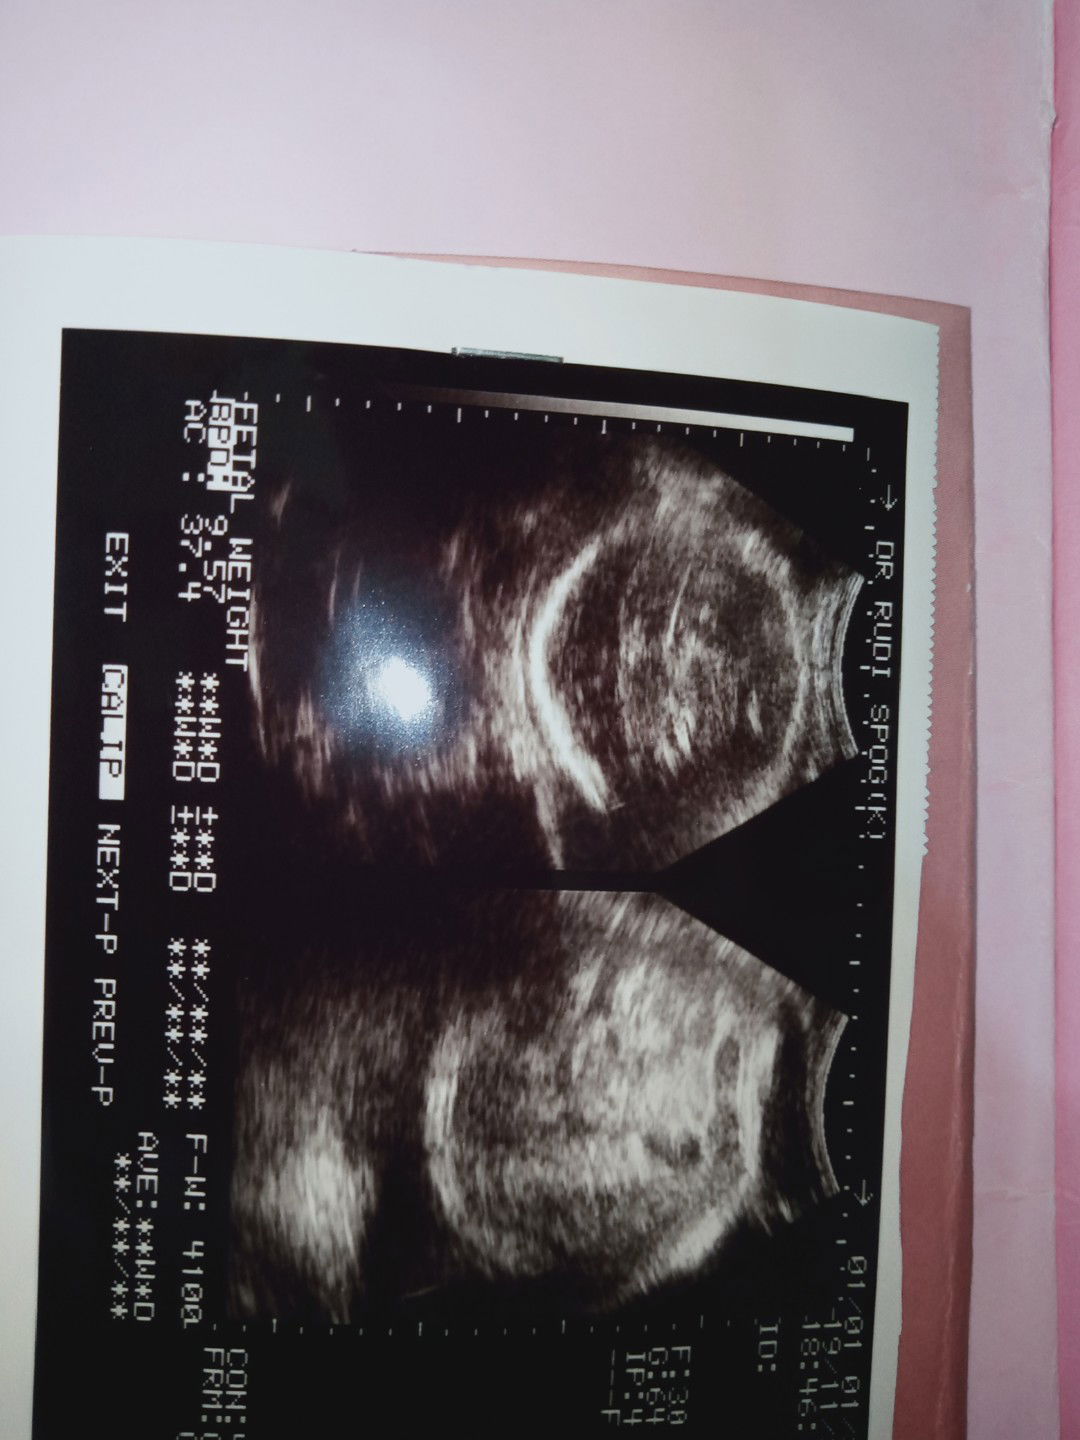

Malam Bun,mw berbagi pengalaman Sekarang qunya kesal bangat sama dokter langganan sy,Minggu kemarin USG berat bayi 3.4kg. Disuruh datang seminggu lagi karena hplnya masih kemarin. Tadi USG lagi hasilnya plasenta udah pengapuran dan berat dedenya udah 4,1kg. Dan disarankan besok sampai batas 3hri waktu diskusi sama paksu untuk SC. Yg jadi masalah sy minta induksi tidak diperbolehkan Krn bayi besar takut membahayakan janin tersebut katanya batas bayi induksi berat3.5kg,yg sy heran knp pas Minggu kemarin waktu 39w berat3.4kg ga ad omongan untuk induksi,? Sy masih mengharapkan lahiran normal Krn dedeny masih aktif bergerak, Sedih rasanya klw harus SC bunda.padahal tenaga sy masih kuat,masalahnya udah 40w1d Lum ad tanda2 mw launching dedenya. Semoga Tuhan campur tangan dalam persalinanku,dan masih ad mukjizat. Amin